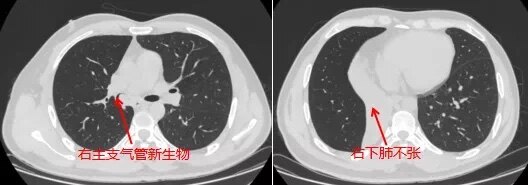

????近日,我院呼吸與危重癥醫(yī)學(xué)科在學(xué)科帶頭人羅少華主任醫(yī)師帶領(lǐng)下,成功為一名右主支氣管下段占位病變患者施行河源地區(qū)首例硬質(zhì)支氣管鏡下支氣管新生物鉗除+激光消融術(shù)。????患者高某,男,45歲,因“咳嗽、咳痰5月”入院。胸部增強(qiáng)CT提示:1、右主支氣管下段、右中間支氣管占位性病變,并右肺下葉不張;2、雙肺上葉、左肺下葉多發(fā)結(jié)節(jié)灶。影像學(xué)檢查提示惡性腫瘤導(dǎo)致的阻塞性肺不張,但初步的病理活檢并不支持,經(jīng)氣管鏡組織活檢提示:(右主支氣管)黏膜慢性潰瘍并肉芽腫形成。羅少華主任查房指出,患者為中青年男性,無吸煙史,右主支氣管至右中間支氣管占位,并右下葉肺不張,氣管鏡下活檢病理未見腫瘤改變,可能跟取材表淺有關(guān),但不完全排除非腫瘤性病變,建議行硬質(zhì)支氣管鏡下支氣管腫物鉗除+激光消融術(shù),取較大塊組織行病理檢查以明確診斷,同時(shí),解除其氣道梗阻。???????對(duì)硬質(zhì)支氣管鏡下支氣管腫物介入治療術(shù)的必要性和并發(fā)癥充分知情后,患者及家屬簽署同意書,羅少華主任帶領(lǐng)學(xué)科團(tuán)隊(duì)在手術(shù)室全麻下為患者成功實(shí)施了手術(shù),對(duì)氣道腫物進(jìn)行清除,術(shù)中出血少,未出現(xiàn)氣胸等并發(fā)癥,術(shù)后患者恢復(fù)良好,咳嗽減少,呼吸困難明顯緩解。????????數(shù)日后,手術(shù)標(biāo)本病理回報(bào):慢性化膿性炎癥并肉芽腫形成,見大量多核巨細(xì)胞,胞質(zhì)內(nèi)見圓形折光樣物,考慮新型隱球菌感染;肺泡灌洗液mNGS發(fā)現(xiàn)新型隱球菌系列。血隱球菌莢膜抗原(+)也支持上述診斷。因隱球菌感染經(jīng)常累及中樞神經(jīng)系統(tǒng),在完善腦脊液檢查后,遂予針對(duì)性抗真菌治療,獲得滿意效果。????羅少華主任指出,經(jīng)硬質(zhì)支氣管鏡下對(duì)該患者氣道占位進(jìn)行鉗除及激光消融術(shù),既明確了診斷,又進(jìn)行了有效的局部治療,消除了肺不張,可謂一舉多得。新型隱球菌多表現(xiàn)為肺內(nèi)結(jié)節(jié)、團(tuán)塊或斑片影,而像該患者主要表現(xiàn)為氣管內(nèi)占位而并發(fā)肺不張者,實(shí)屬少見,此時(shí),臨床很難與肺部腫瘤相鑒別。????硬質(zhì)支氣管鏡(硬鏡)是現(xiàn)代醫(yī)學(xué)設(shè)備的一種,然而近三十年來,隨著軟體纖維光學(xué)支氣管鏡(纖支鏡)在臨床的推廣,硬鏡的應(yīng)用已明顯減少。但是近年來隨著呼吸介入病學(xué)發(fā)展,硬質(zhì)支氣管鏡作為介入通道允許纖支鏡及其他器械進(jìn)入氣道內(nèi),經(jīng)纖支鏡的目鏡觀察定位,在直視下進(jìn)行支架植入或取出、激光、冷凍、電切、取異物等多種操作。因此,硬鏡是現(xiàn)代介入性肺病學(xué)的主要工具,是呼吸科醫(yī)生應(yīng)當(dāng)掌握的一項(xiàng)重要技術(shù)。????我院呼吸與危重癥醫(yī)學(xué)科成功開展硬質(zhì)支氣管鏡下支氣管新生物鉗除+激光消融術(shù),標(biāo)志著我院在呼吸介入診療技術(shù)方面又有了新的突破,并進(jìn)一步豐富了呼吸介入治療手段,將為河源及周邊地區(qū)支氣管良惡性病變患者帶來更多的便利和福音。